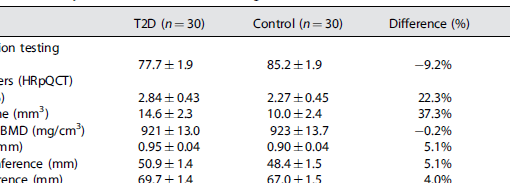

Densitometry and imaging techniques are currently used in clinical settings to measure bone quantity and spatial structure. Recently, Reference Point Indentation has opened the possibility of directly assessing the mechanical characteristics of cortical bone in living individuals, adding a new dimension to the assessment of bone strength. Impact microindentation was specifically developed for clinical studies and has been tested in several populations where there are discrepancies between bone density and fracture propensity, such as type 2 diabetes, atypical femoral fracture, stress fractures, glucocorticoid treatment, patients with osteopenia and fragility fractures, and individuals infected with HIV, among others. Microindentation will complement, not replace, existing bone analysis methods, particularly where bone mineral density does not fully explain fracture propensity. The available evidence provides solid proof of concept; future studies will fully define the role of microindentation for the assessment of bone health both in clinics and in research.